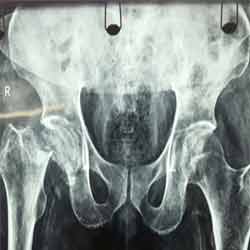

Case:8 Polytrauma

Patient having closed segmented fracture midshaft & lower 1/3 Tibia with closed fracture superior & inferior pubic rami right side with pelvis fracture following vehicular accident wastreated with intramedullary nail for fracture tibia and external fixator for fracture pelvis.

Ex fix with frame